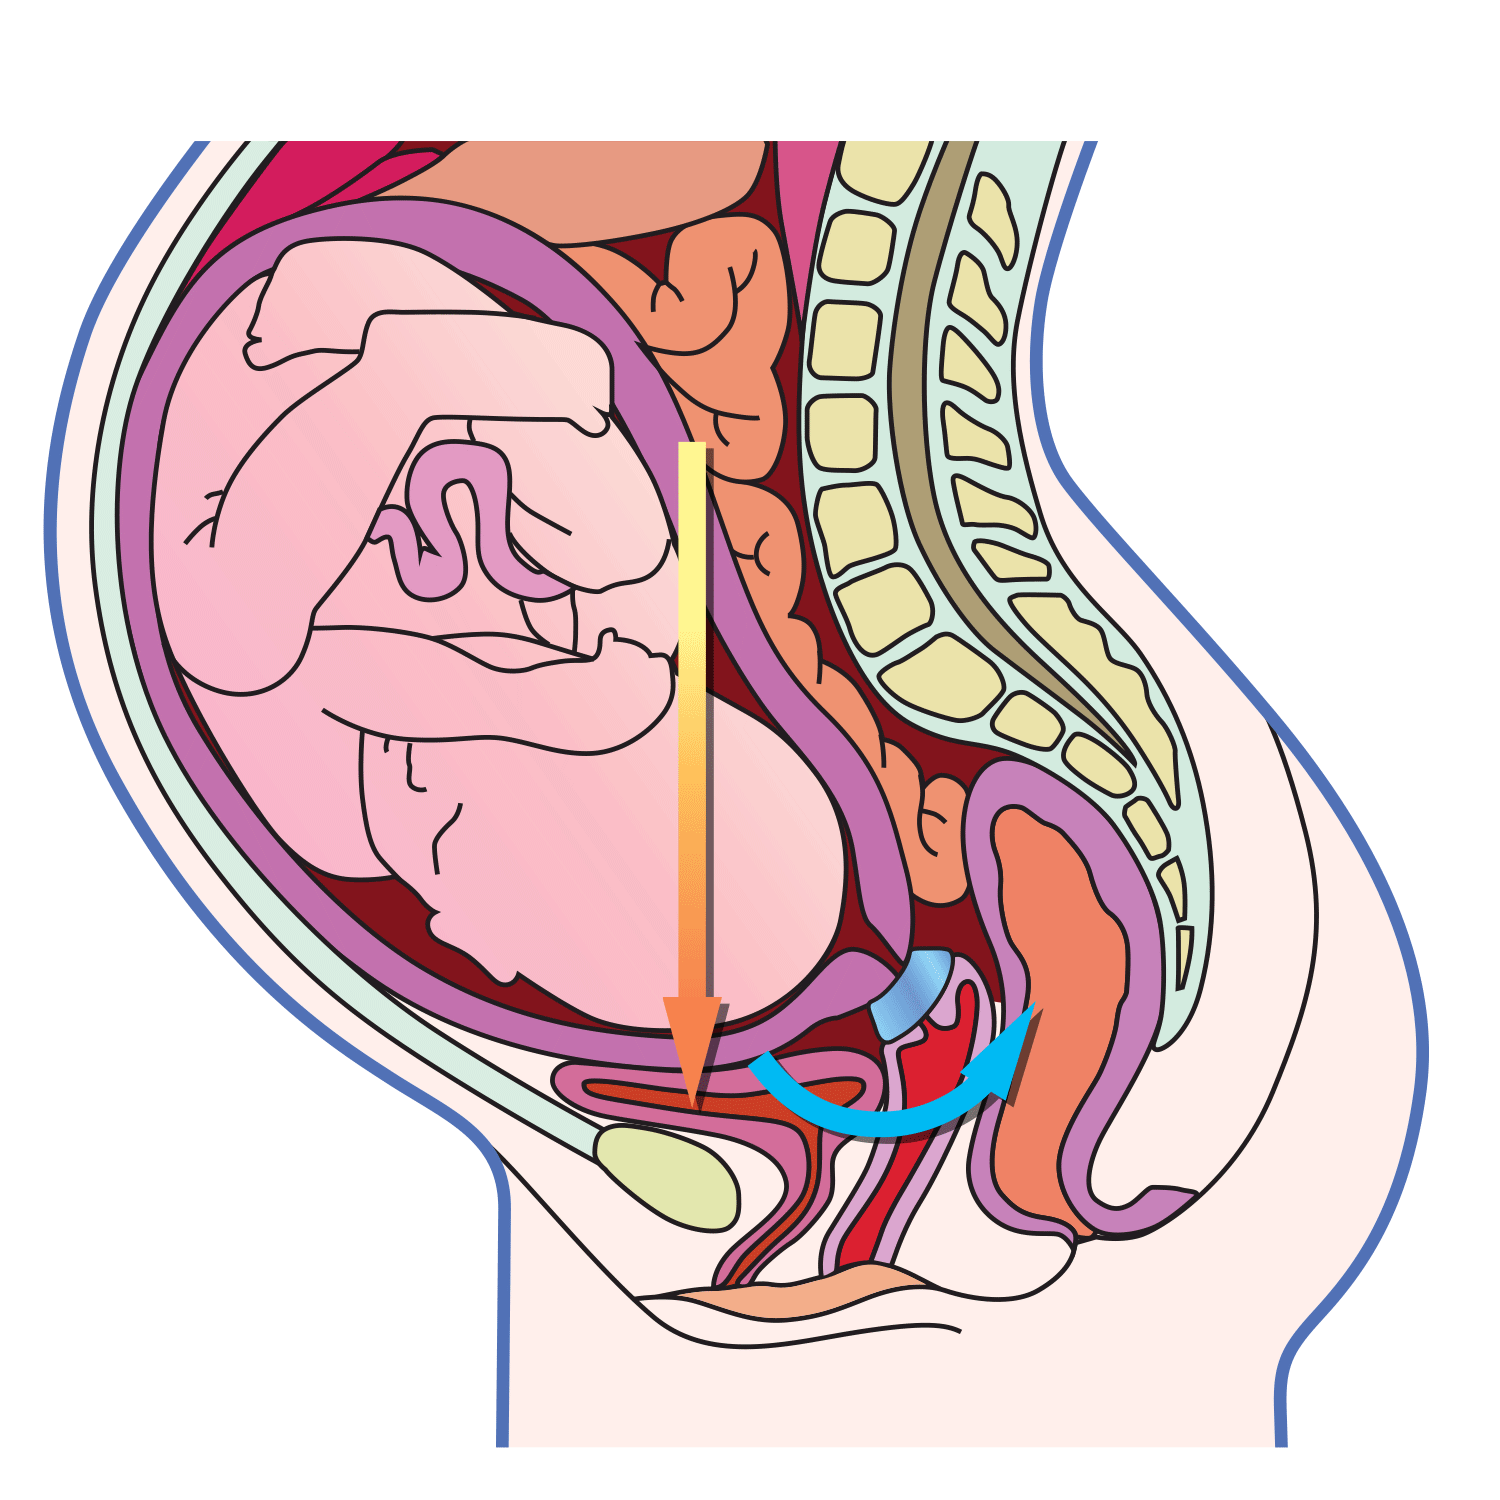

Это правильный ответ. Акушерский пессарий Доктор Арабин замыкает шейку матки стенками центрального отверстия пессария и препятствует открытию внутреннего маточного зева [4], уменьшает гидравлическое давление плодного пузыря на внутренний зев (давление плодного пузыря смещается на переднюю стенку матки) за счет изменения маточно-цервикального угла, сохраняет слизистую пробку в цервикальном канале и поддерживает состояние иммунологического барьера между плодным яйцом и вагинальной микрофлорой, снижает вероятность инфицирования [16].